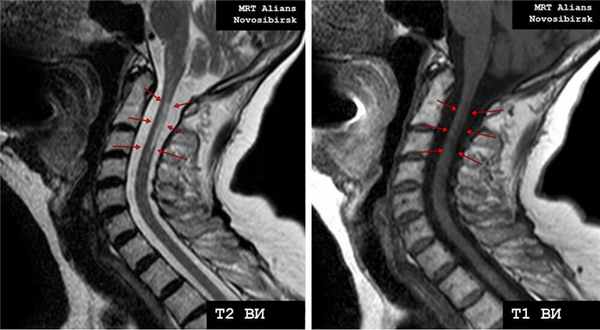

Рис. 2. МРТ шейного отдела позвоночника (дорзальная экструзия /грыжа/ межпозвонкового диска С5/6).

Рис. 3. МРТ шейного отдела позвоночника - очаг демиелинизации (рассеянный склероз).

Рис. 4. МРТ шейного отдела позвоночника - гидросирингомиелия.